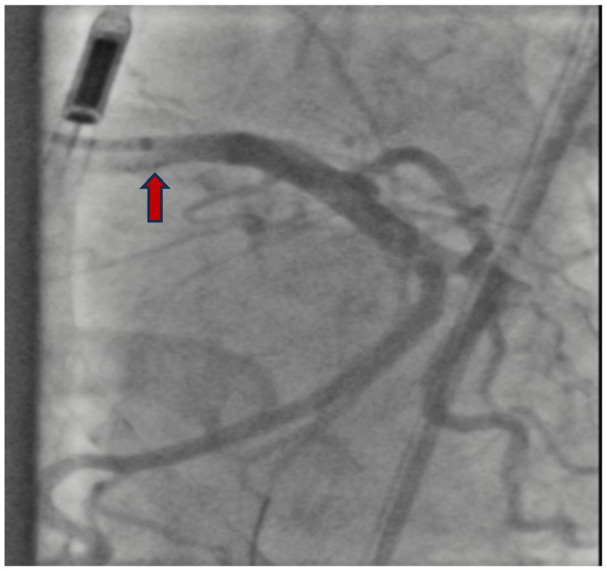

Takayasu's arteritis (TAK) is a rare, large-vessel vasculitis that typically involves the aorta and its major branches. Patients may experience coronary involvement, most commonly the left main coronary ostia. Patients with coronary artery occlusion often require emergent revascularization; however, there is debate regarding the optimal timing and type of surgical intervention in the setting of TAK. Herein we describe a 32-year-old female presenting with non-ST elevation myocardial infarction (NSTEMI) who underwent percutaneous intervention (PCI) with drug-eluting stent (DES) placement and was subsequently diagnosed with TAK. A 32-year-old female presented to the emergency department with chest pressure and dyspnea. Her electrocardiogram findings and troponin elevation were consistent with NSTEMI and she underwent coronary angiography with DES placement. During angiography, aortic insufficiency was noted. Transesophageal echocardiogram confirmed intimal thickening of the aortic root with aortic regurgitation. She was diagnosed with TAK, started on high-dose steroids, and transferred to a tertiary care center for rheumatology consultation. This patient's clinical course raised several questions regarding surgical intervention in TAK. The optimal timing of surgery and preferred approach (endovascular intervention vs coronary artery bypass grafting [CABG]) were specifically critiqued. While endovascular intervention (PCI with angioplasty or stent) is typically less invasive than CABG, it may be associated with a higher risk of postsurgical re-stenosis and studies are conflicting regarding the optimal approach. Further research is necessary to determine the long-term efficacy and safety of these interventions, as well as their timing in the overall management plan.